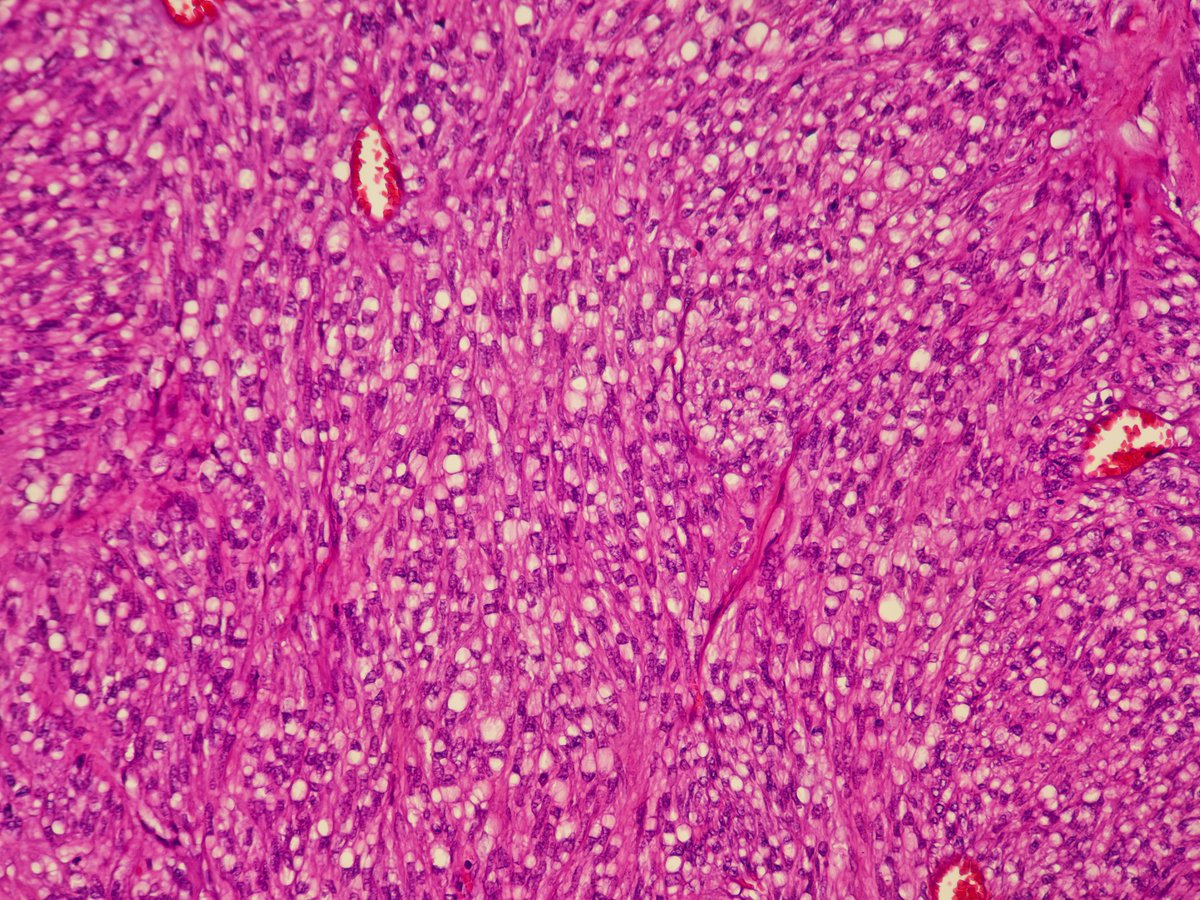

GIST imitating archipelago growth pattern of renal oncocytoma 🔬 Also 👀 beautiful paranuclear vacuoles characteristic of gastrointestinal stromal tumors. The beauty of #pathology #GUPath + #BSTPath = ♥️

GIST imitating archipelago growth pattern of renal oncocytoma 🔬

Also 👀 beautiful paranuclear vacuoles characteristic of gastrointestinal stromal tumors.